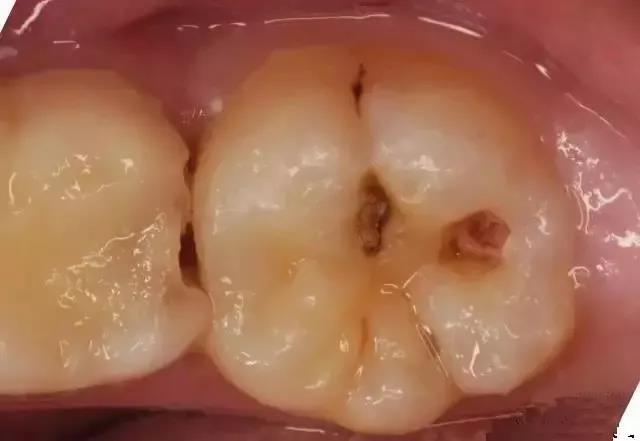

02 中龋

当您吃糖时,感觉酸疼,您说:“没关系,不是很疼。”

牙医却说:“这时病变已经破坏到牙本质浅层了,牙齿已经有龋洞形成,对酸甜食物敏感,需要做充填治疗。”

03 深龋

当您进食时,没法咬食物,您说:“还好,可以用另外一边牙齿咬。”

牙医告诫说:“病变已经破坏到了牙本质深层,牙齿有较深的龋洞,温度刺激,化学刺激以及食物进入龋洞时均引起疼痛,此时,及时做充填治疗的话还来得及保住牙髓。”